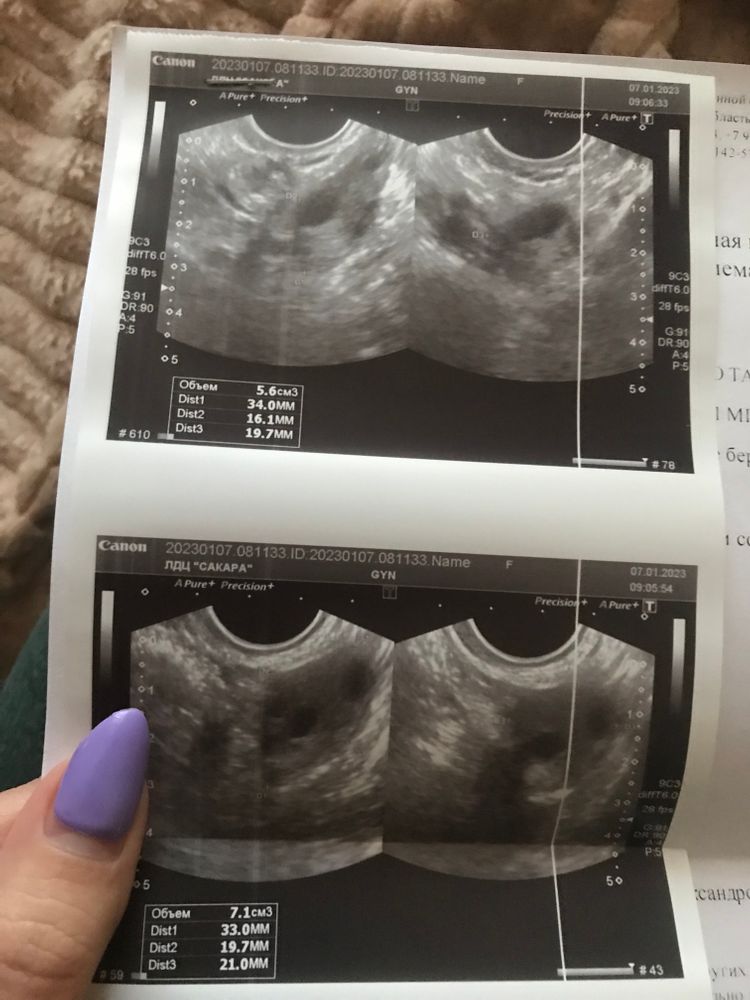

Фотографии яичников, а не матки.

Фолликулы атретические (на начало нового цикла совершенно не похоже) .

Екатерина, Со 2 по 4 дц мелкофолликуляная структура яичников. фолликулы 2-6мм.

7-12мм считаются атретическими.